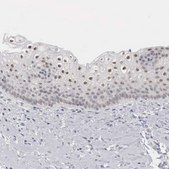

All Prestige Antibodies Powered by Atlas Antibodies are developed and validated by the Human Protein Atlas (HPA) project and as a result, are supported by the most extensive characterization in the industry.

The Human Protein Atlas project can be subdivided into three efforts: Human Tissue Atlas, Cancer Atlas, and Human Cell Atlas. The antibodies that have been generated in support of the Tissue and Cancer Atlas projects have been tested by immunohistochemistry against hundreds of normal and disease tissues and through the recent efforts of the Human Cell Atlas project, many have been characterized by immunofluorescence to map the human proteome not only at the tissue level but now at the subcellular level. These images and the collection of this vast data set can be viewed on the Human Protein Atlas (HPA) site by clicking on the Image Gallery link. We also provide Prestige Antibodies® protocols and other useful information.

• IHC tissue array of 44 normal human tissues and 20 of the most common cancer type tissues.